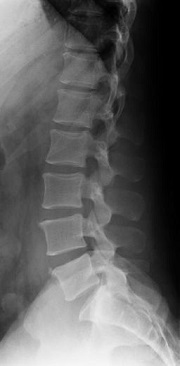

1- رادیوگرافی ساده X-ray

گر چه تصاویر حاصله از یک رادیوگرافی ساده فقط استخوان را نشان میدهند ولی میتوانند اطلاعات مهمی مثل شکستگی استخوان، تغییرات ناشی از روند پیری در مهره و تغییر شکل و دفرمیتی های ستون مهره را نشان دهد .